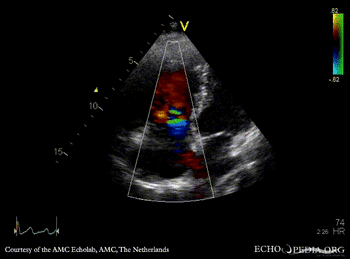

| A4CH: ASD type II | A4CH: enlargement of right ventricle and right atrium |